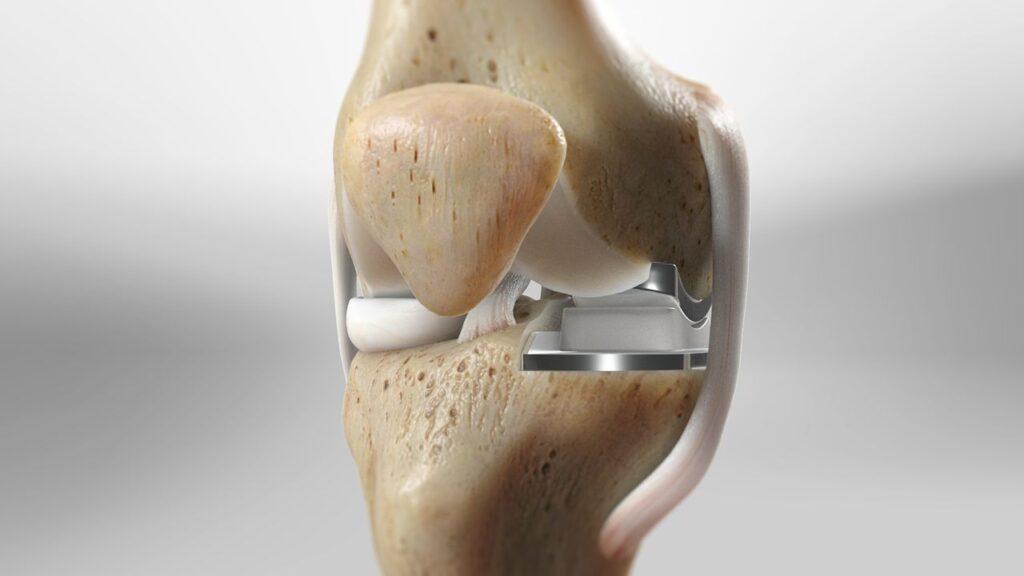

Resurfacing : Damaged bone and cartilage are removed from the femur, tibia and patella. Metal components are then attached to the ends of these bones and a plastic spacer is placed in between them to create a smooth surface for movement.

Partial knee replacement (PKR), also known as unicondylar or unicompartmental knee replacement, is a surgical procedure that replaces only the damaged portion of the knee joint, while preserving the healthy parts. Unlike total knee replacement, PKR focuses on restoring function by targeting one or two specific compartments of the knee.